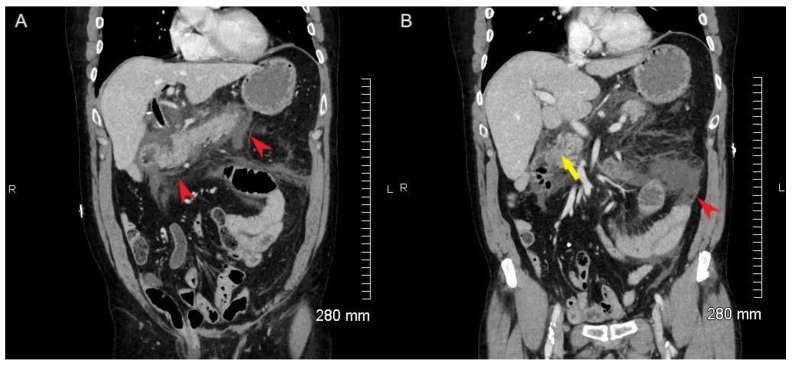

Initial laboratory testing showed critically elevated lipase and elevated white blood cell count with low sodium. ALP, ALT, AST, and bilirubin were normal. There was no evidence of bacteremia or sepsis. Initial ultrasound was equivocal for gallstones. Initial CT of the abdomen and pelvis demonstrated peripancreatic fat stranding and heterogenous appearance of the parenchyma consistent with acute pancreatitis (Figure 1, red arrowheads) but no definite choledocholithiasis. The CBD measured 8 mm with slight mural thickening. The biliary tree was prominent with abnormal wall enhancement, but no definite signs of choledocholithiasis were noted in the CBD (Figure 1B, yellow arrowhead). A repeat biliary ultrasound demonstrated sludge and choledocholithiasis in the CBD.